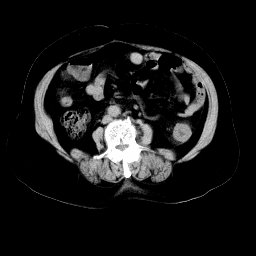

以下是引用余辉在2008-11-9 9:47:00的发言:[br]各层面均可见降结肠管壁增厚,管腔狭窄,中部层面可见管壁明显增厚区,结合病史多考虑降结肠癌,溃疡性结肠炎不除外,建议进一步检查